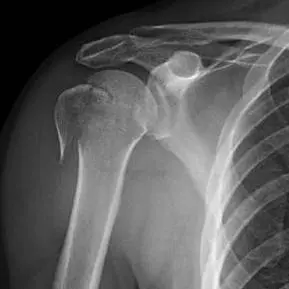

كسر الحدبة الكبرى هو إصابة شائعة تصيب الجزء العلوي من عظم العضد، حيث تتصل عضلات الكتف الرئيسية. يتضمن علاجه خيارات غير جراحية للحالات البسيطة مثل الراحة والعلاج الطبيعي، أو التدخل الجراحي لتثبيت الكسر في الحالات الأكثر تعقيدًا وإزاحة، بهدف استعادة وظيفة الكتف وتجنب المضاعفات.